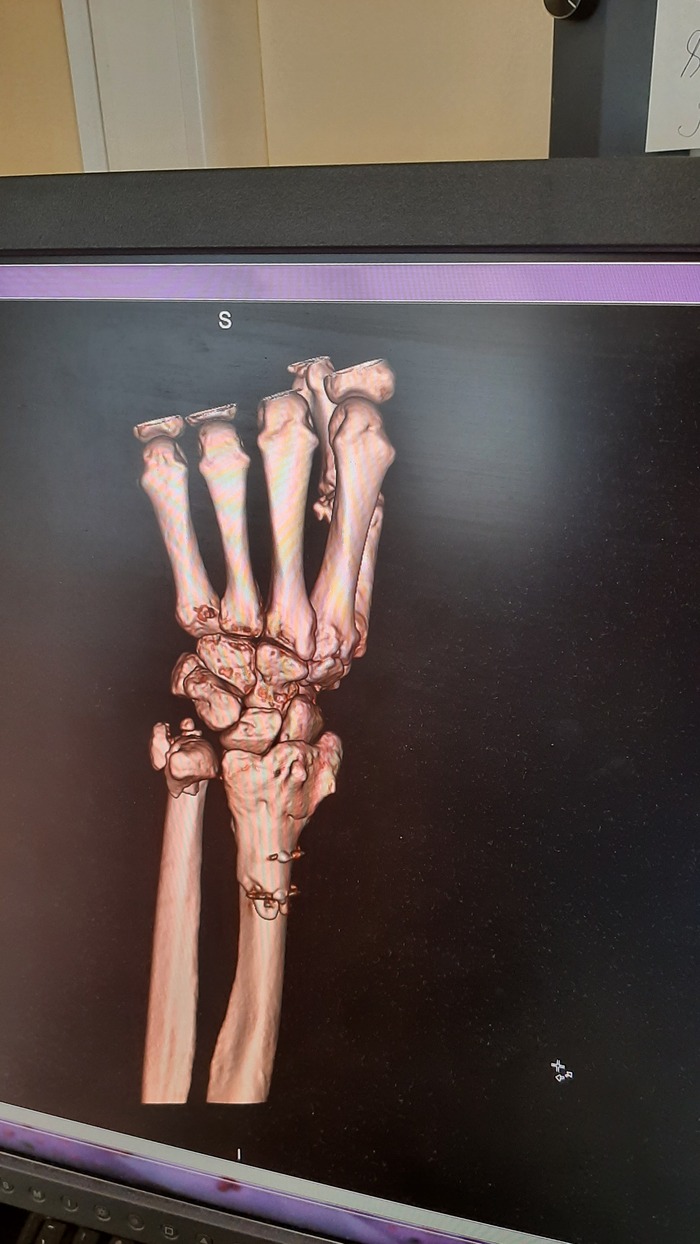

Ну и очень много рентгеновских снимков